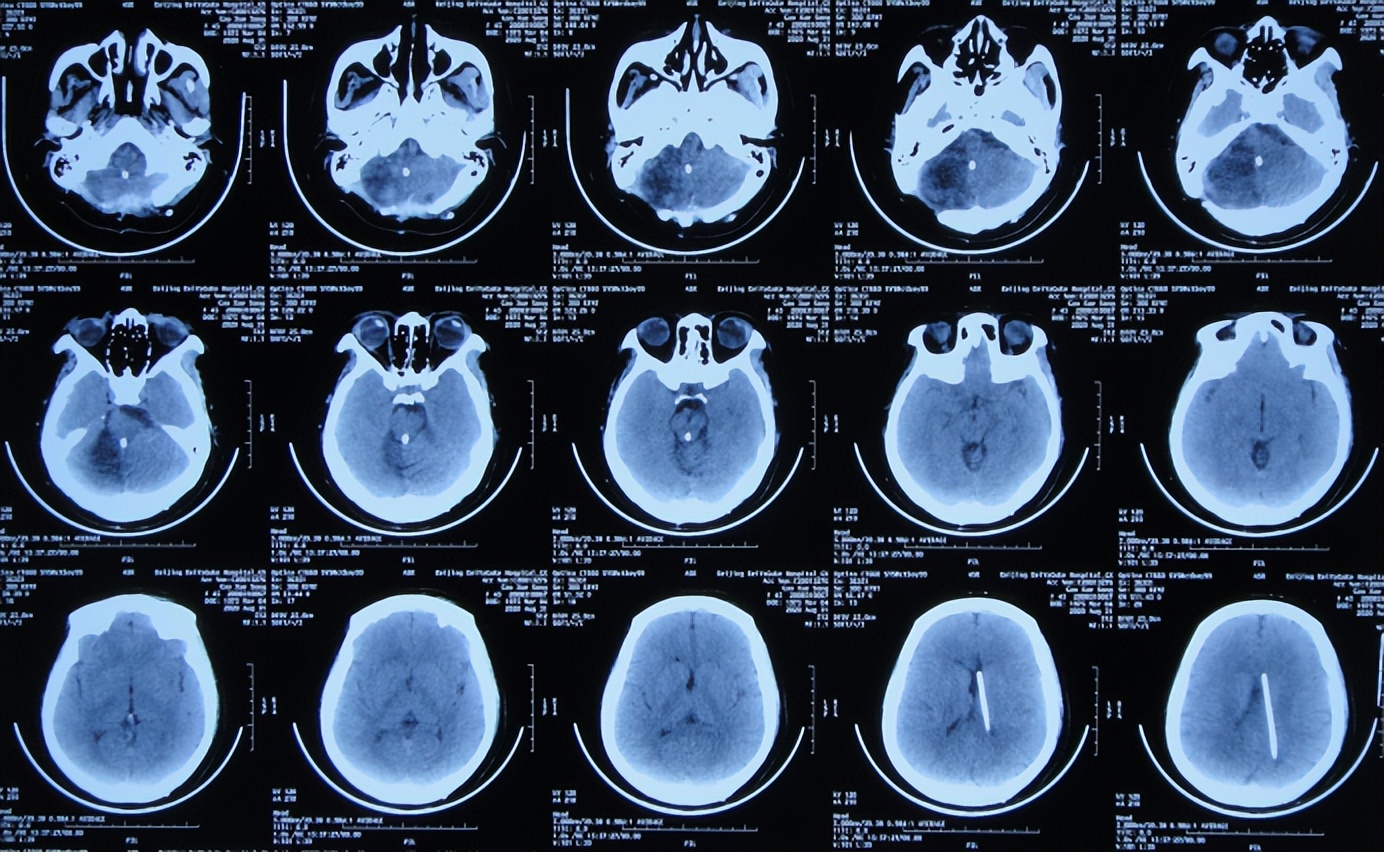

2014年7月1日(入院治疗111天),进行了侧脑室、四脑室腹腔分流术。

2014年7月18日(李小勇脑脊液科治疗120天)出院回家,出院时:颅内感染已治好,患者神志清楚仍卧床,偶有恶心,能简单对答,瘫痪的右侧肢体变得能简单遵嘱活动,但左上肢差,仍鼻饲流食(图-25);但遗留了听神经瘤术后右眼失明,左侧嘴角偏斜。

出院后6年即2020年8月31日,当地医院复查头颅CT示无异常(图-31)。

图-31:2020年8月31日头颅CT